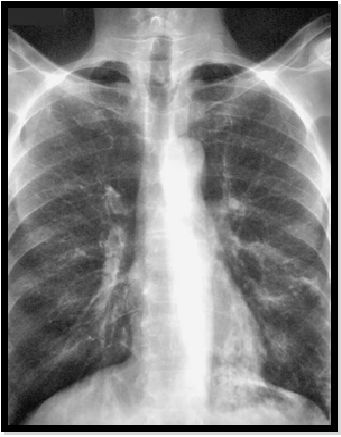

图8:胸部X线片显示由于ABPA中的支气管粘液堵塞导致左下叶中的管状阴影。

abp在医学是什么意思如何区分4种类型的肺曲霉菌病影像学表现?_https://www.jmylbn.com_新闻资讯_第11张